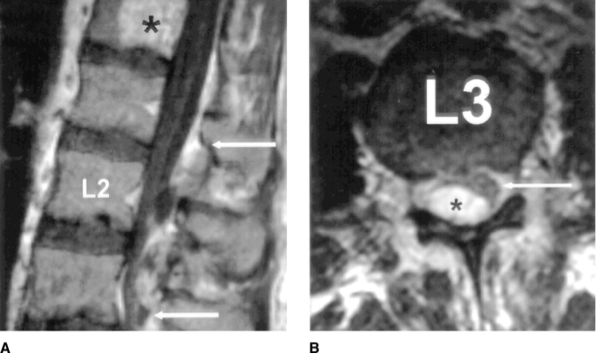

- Imaging: Definitive diagnosis made by MRI, with sensitivity and specificity above 90%. 7, 8 Worse outcomes with: central stenosis >50% and abscess length >3 cm. 9

A: arrows delineate abscess margins; B: asterisk – abscess, arrow – thecal sac

http://www.jaaos.org/content/12/3/155/F1.expansion